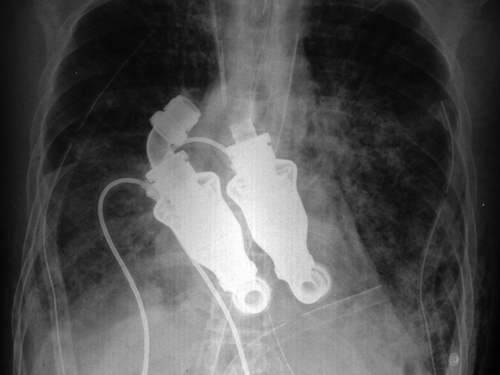

Doctors from the Texas Heart Institute have successfully replaced a patient's heart with a device that keeps the blood flowing, thereby allowing him to live without a detectable heartbeat or even a pulse. Here's how it works:

The turbine-like device, that are simple whirling rotors, developed by the doctors does not beat like a heart, rather provides a ‘continuous flow’ like a garden hose.

However, when doctors put a stethoscope to his chest, no heartbeat or pulse can be heard (only a ‘humming’ sound)—which “by all criteria that we conventionally use to analyze patients”, Doctor Cohn said, he is dead.

This is proof that “human physiology can be supported without a pulse”.